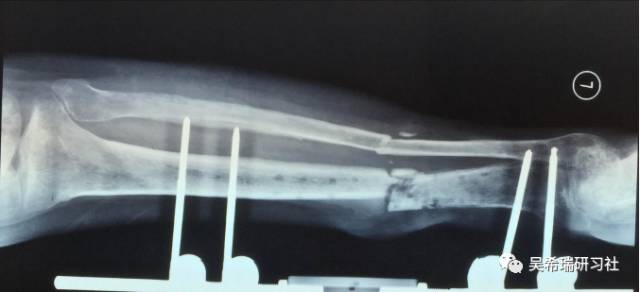

小腿骨折继发感染骨髓炎反复皮瓣9个月未下地骨质疏松继发肥胖

TIPS:9个月反复皮瓣未下地骨质严重疏松病灶清除后应用表面羟基磷灰石涂层骨圆钉半开放植骨 + 骨搬移骨水泥设计为自行吐出伤口开放换药走路骨质改善、骨愈合治疗足下垂